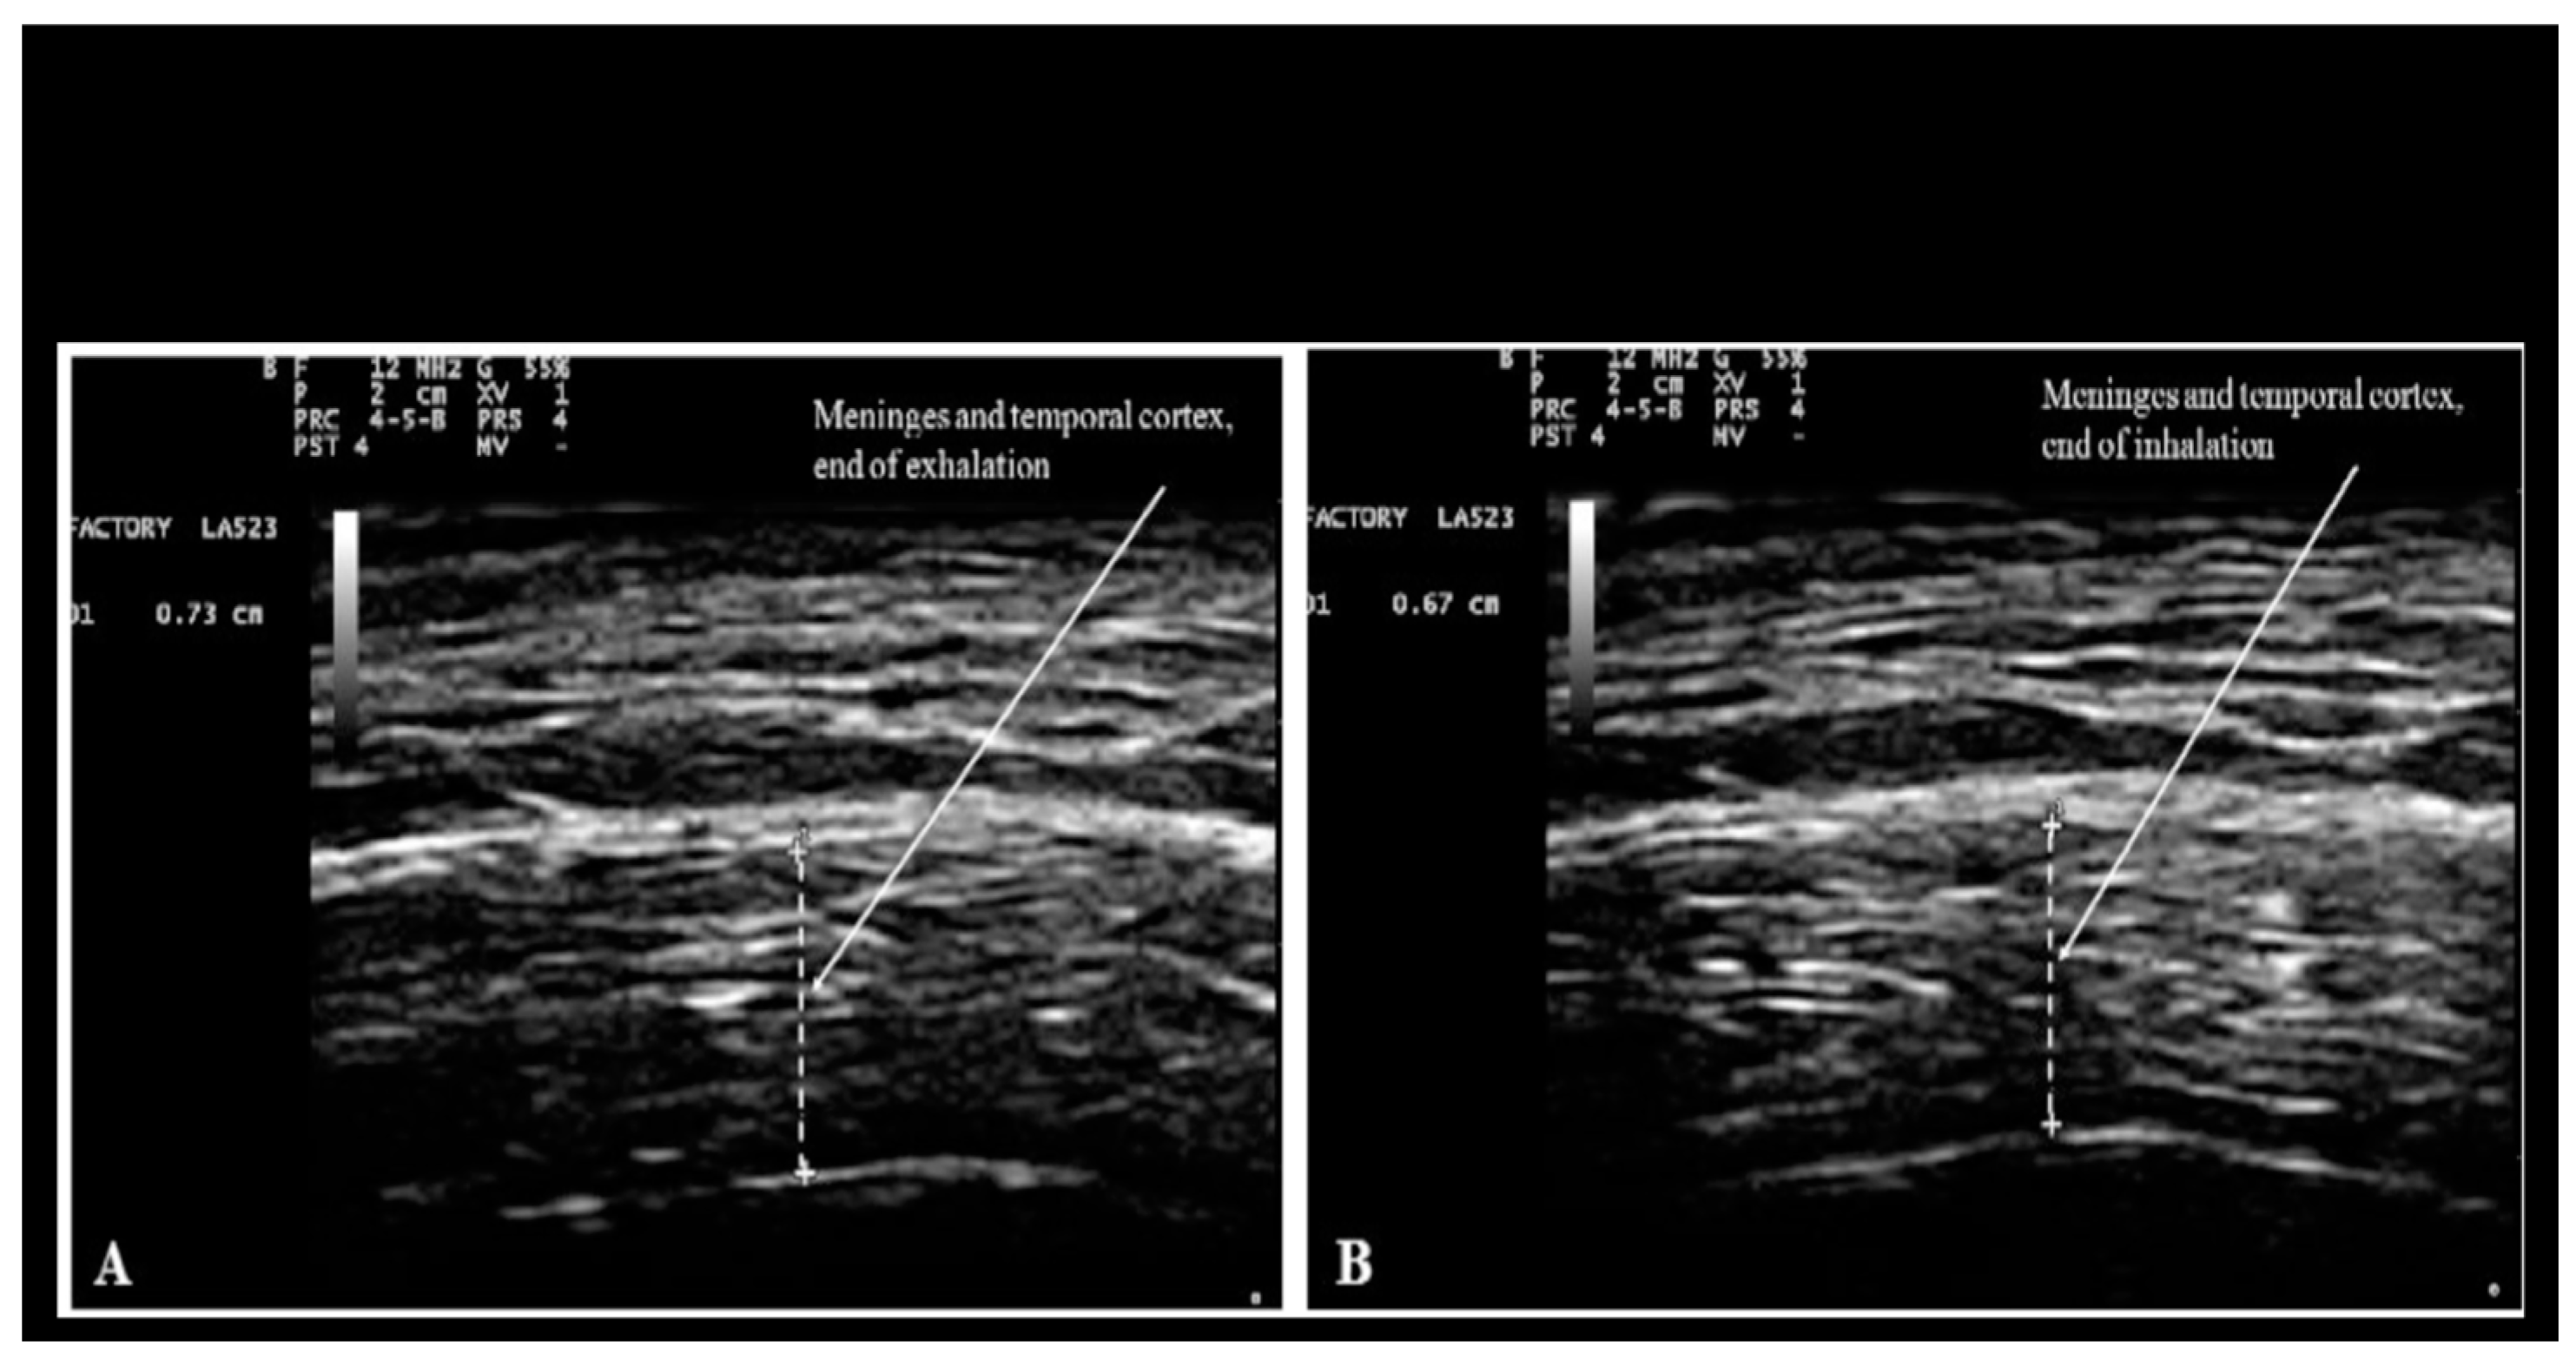

- Ruggiero M. Application of ultrasonography to Neuro-COVID-19. Int J Radiol Radiat Ther. 2022;9(3):99‒103. https://medcraveonline.com/IJRRT/IJRRT-09-00331.pdf. [CrossRef]

- Ruggiero M, Magherini S, Fiore MG, Chiarelli B, Morucci G, Branca JJ, Gulisano M, Pacini S. Transcranial sonography: a technique for the study of the temporal lobes of the human and non-human primate brain. Ital J Anat Embryol. 2013;118(3):241-55. https://pubmed.ncbi.nlm.nih.gov/24640587/.